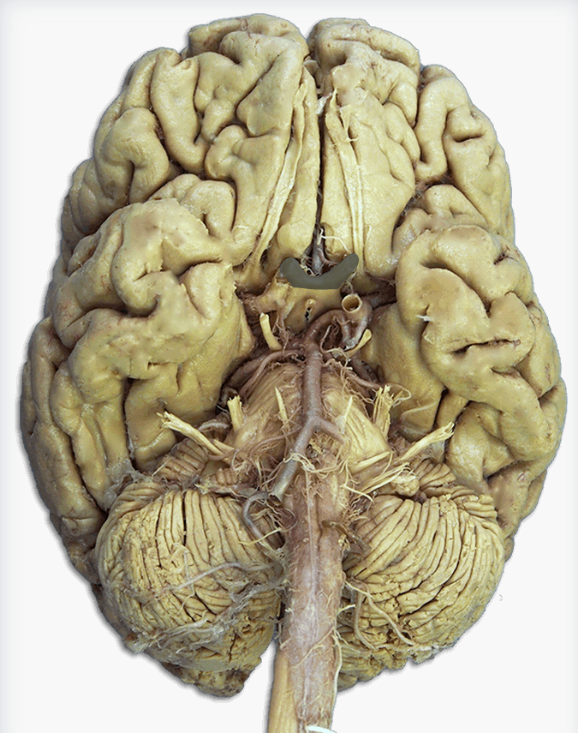

Label this cerebral artery

Basilar artery

Label this cerebral artery

Anterior communicating artery

Label this cerebral artery

Middle Cerebral Artery

Label this cerebral artery

Posterior Cerebral Artery

Label this cranial nerve

Olfactory (CN I) nerve

Label this cranial nerve

Optic (CN II) nerve

Label this cranial nerve

Oculomotor (CN III) nerve

Label this cranial nerve

Trochlear (CN IV) nerve

Label this cranial nerve

Trigeminal (CN V) nerve

Label this cranial nerve

Abducens (CN VI) nerve

Label this cranial nerve

Facial (CN VII) nerve

Label this cranial nerve

Vestibulocochlear (VIII) nerve

Label this cranial nerve

Glossopharyngeal (CN IX) nerve

Label this cranial nerve

Vagus (CN X) nerve

Label this cranial nerve

Accessory (CN XI) nerve

Label this cranial nerve

Hypoglossal (CN XII) nerve